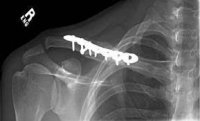

Körpücük sümüyünün sınıqları

Müalicə

Körpücüyün proksimal 1/3 hissəsinin sınıqlarında ortopedik cərrahın cəlb edilməsi mütləqdir, belə ki, bu tip zədələnmə